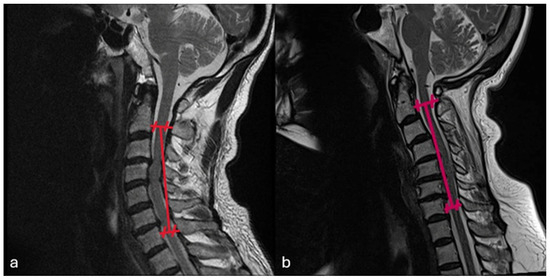

Background and Objectives: The assessment of cervical lordosis is essential for surgical planning and outcome prediction in patients with cervical spine pathology. This study aims to evaluate the accuracy of cervical lordosis measurements obtained on supine CT and MRI relative to standing [...] Read more.

Background and Objectives: The assessment of cervical lordosis is essential for surgical planning and outcome prediction in patients with cervical spine pathology. This study aims to evaluate the accuracy of cervical lordosis measurements obtained on supine CT and MRI relative to standing lateral radiographs. Materials and Methods: In this retrospective review, 108 patients who underwent standing lateral radiographs, supine CT, and MRI within a 30-day period were identified. C2–C7 Cobb angles were measured on each modality. Using upright radiographs as the reference standard, the predictive capability of both supine CT and supine MRI in classifying kyphotic versus non-kyphotic alignment was calculated. Results: Standing radiographs demonstrated significantly greater lordosis than supine imaging, with mean paired differences of 6.2° versus CT and 5.0° versus MRI (both p < 0.001); however, strong correlations were observed (with CT: r = 0.75; with MRI: r = 0.72; both p < 0.001). Further, CT-based measurements predicted X-ray Cobb angles with an R2 value of 0.57 (estimated X-ray Cobb angle = 8.24 + 0.74 × (CT Cobb angle), β = 0.74, p < 0.001). MRI-based measurements yielded an R2 of 0.51 (estimated X-ray Cobb angle = 7.59 + 0.71 × (MRI Cobb angle), β = 0.71, p < 0.001). At threshold ≥ 0°, CT achieved a 100% NPV for excluding kyphosis on upright radiographs. MRI achieved an NPV of 100% when the Cobb angle was >1.20°. Conclusions: Supine CT and MRI systematically underestimate cervical lordosis but demonstrate strong predictive correlation with standing radiographs and reliably exclude true kyphotic alignment, with each achieving near-perfect NPV at defined thresholds. In cases where standing radiographs are unavailable or nondiagnostic, supine imaging modalities such as CT and/or MRI, where the cervical region appears nonkyphotic, can safely rule out cervical kyphosis and inform surgical planning; however, in cases where the cervical region appears kyphotic on CT and/or MRI, standing radiographs remain essential for accurate assessment. Full article